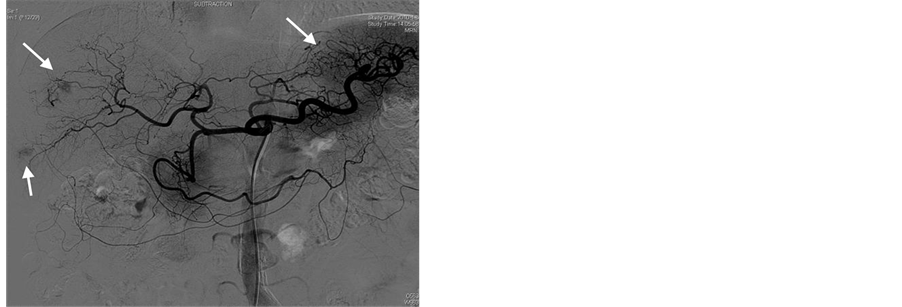

After splenic MWA, a 5.0 French catheter (Terumo, Tokyo, Japan) was inserted into the femoral artery with the Seldinger method after local anesthethia, celiac angiography and selective hepatic arterial angiography were routinely performed to observe the tumor blood-supply, distribution of hepatic arteries and collateral circulation routes (Figure 1(a)), the tip of the catheter was placed at the feeding artery of the tumor, and embolization was performed using an emulsion mixture of lipoidal ultra-fluid (Guerbet, France), perarubicin (50 mg/m2) and DDP (80 mg/m2). The maximum dose for embolization was based on the size of the tumor, blood supply and hepatic function of the patient. When the tumor was filled well with emulsifier, the embolization was terminated (Fig- ure 1(b)).

Figure 1. TACE treatment for a 63-year-old male case of HCC with splenomegaly and thrombocytopenia. (a) Celiac arteriography before TACE showing the tumor blood-supply image, as indicated by the arrowhead; (b) TACE is terminated when the three tumors were filled with emulsifier, as indicated by the arrowhead.